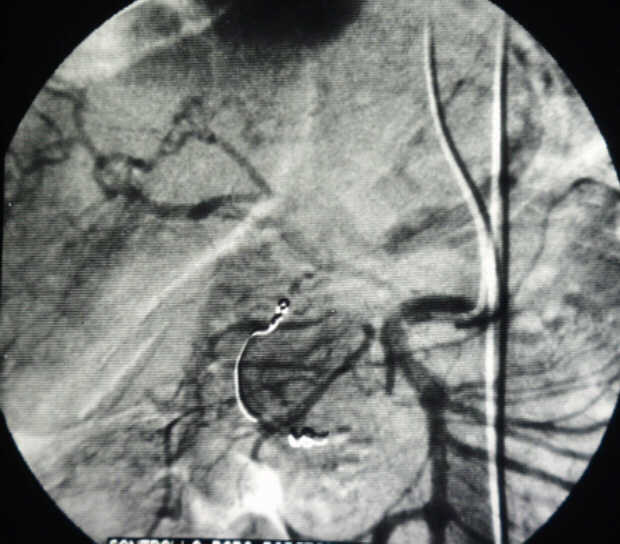

Diagnosis: Angiography

Giuseppe Morelli Coppola, Raffaella Niola, Franco Maglione

Unità Operativa di Radiologia Vascolare ed Interventistica, Azienda Ospedaliera "A. Cardarelli". Napoli, Italy